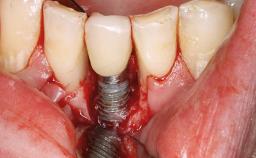

A 24-year-old female patient was treated with an implant- supported crown for single-tooth replacement at site 11. A Straumann Bone Level RC implant (Institut Straumann AG, Basel, Switzerland) was placed with simultaneous bone augmentation, and the periimplant emergence profile was conditioned with a fixed implant-supported provisional crown. After finalization of the mucosal architecture, the clinical situation was transferred by means of a custom impression post for fabrication of an implant-supported screw-retained onepiece crown consisting of a CARES® zirconia abutment (Straumann) with a direct ceramic veneer.